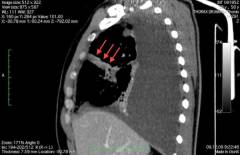

Когда врач формирует мнение о проблеме, назначаются лабораторные анализы и параклинические исследования. Обязательными являются общий анализ крови и мочи. Полезно определение уровня кислорода в крови. Спектр биохимических анализов определяется индивидуально. Рентгенография грудной клетки является обязательным параклиническим исследованием. В сложных случаях могут потребоваться более узконаправленные исследования, такие как бронхоскопия, КТ и МРТ.

Когда врач получает представление о проблеме, назначаются лабораторные анализы и параклинические исследования. Обязательны общий анализ крови и мочи. Полезно определить уровень насыщения крови кислородом с помощью пульсоксиметра. Спектр биохимических анализов зависит от ожидаемых изменений для подтверждения диагноза. Рентгенография грудной клетки является обязательной при болях в груди. При качественном снимке и правильном положении пациента этого может быть достаточно для диагноза. Однако, если клиническая картина не соответствует предполагаемым заболеваниям, требуются более сложные исследования, такие как бронхоскопия, ФЭГДС, торакоскопия, медиастиноскопия, КТ и МРТ.

Диагноз эмпиемы плевры ставится на основе клинических данных, рентгенографии, компьютерной томографии (КТ) и ультразвукового исследования (УЗИ). При перкуссии выявляется притупление звука над областью гноя и коробочный звук в области газа (при анаэробной флоре). Аускультация показывает ослабление или отсутствие дыхательных звуков и шум трения плевры. На рентгенограмме виден уровень жидкости или затемнения при осумкованных плевритах. КТ уточняет локализацию процесса, выявляет фиброз, оценивает степень поражения легочной ткани и возможный источник воспаления. УЗИ используется для предварительной оценки содержимого плевральной полости и мониторинга динамики.

Диагностика

Диагностика затруднена из-за глубокой локализации гнойного процесса. На рентгенографии могут быть видны признаки поднятия диафрагмы, плеврита и гидроторакса. Ультразвуковое исследование надпеченочного, наджелудочного и надселезеночного пространства иногда позволяет обнаружить абсцесс, но требует тщательного поиска. Окончательный диагноз устанавливается с помощью компьютерной или магнитно-резонансной томографии, где в поддиафрагмальном пространстве виден ограниченный гнойный очаг.